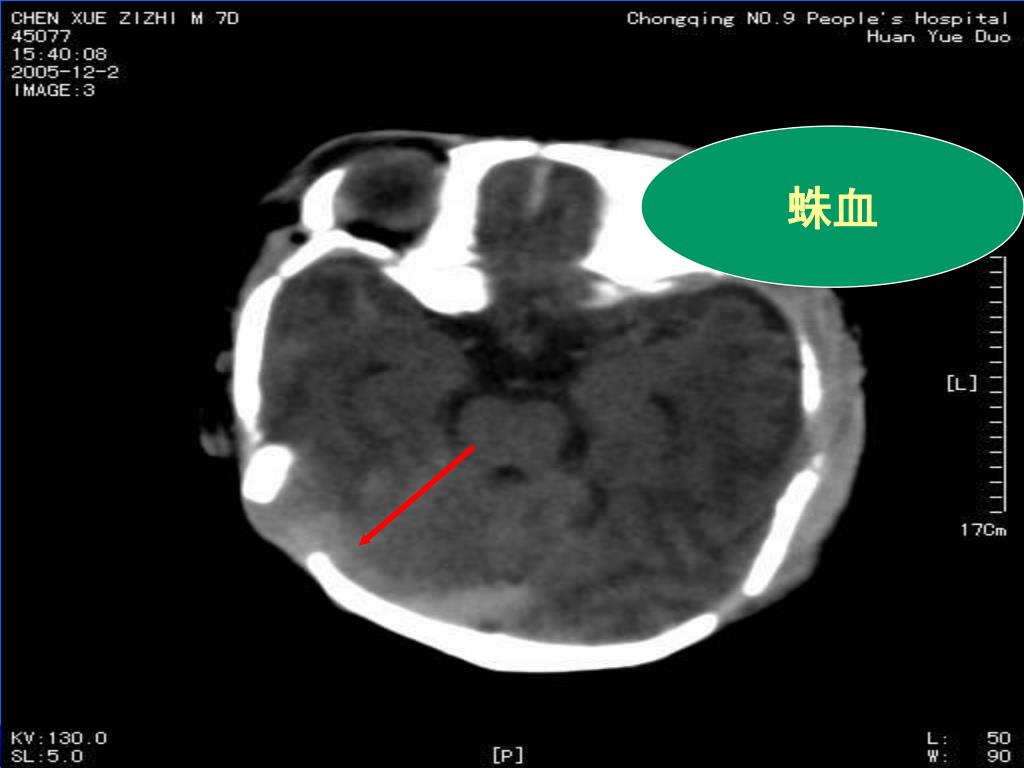

21. 蛛血

22. 蛛血

23. 蛛血

16. (2)正常新生儿,直窦及纵裂池区CT可表现为线状略高密度区。当蛛血时,此区密度增高,宽度增加,且宽窄不一,可呈前宽后窄或前窄后宽及不规则形。其宽度≥5mm,可确诊为新生儿蛛血。(2)正常新生儿,直窦及纵裂池区CT可表现为线状略高密度区。当蛛血时,此区密度增高,宽度增加,且宽窄不一,可呈前宽后窄或前窄后宽及不规则形。其宽度≥5mm,可确诊为新生儿蛛血。